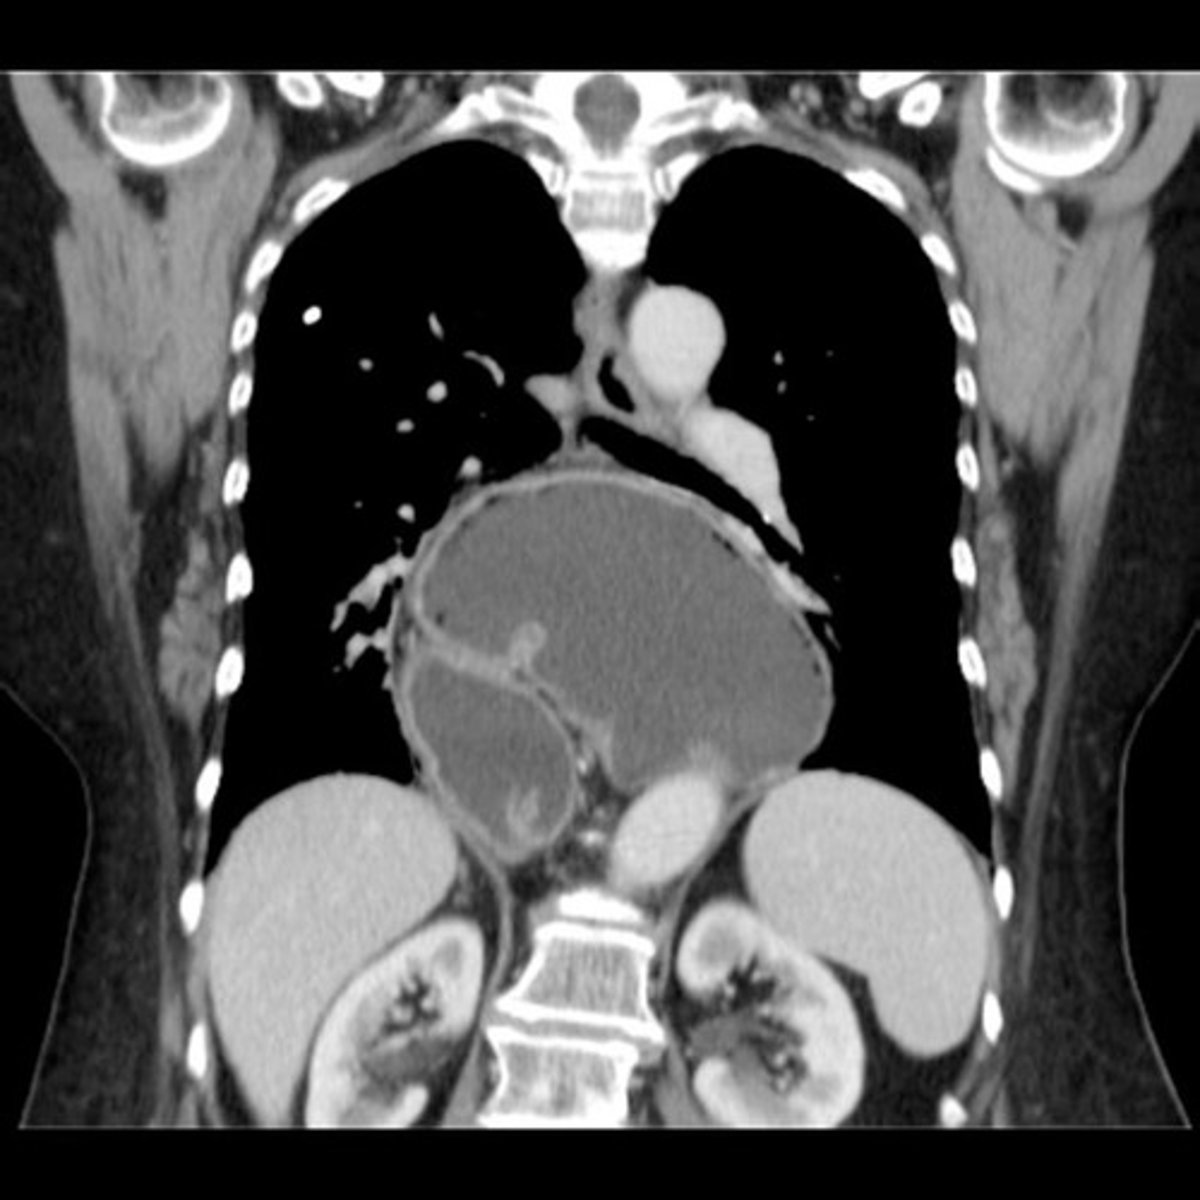

Paraesophageal hernia CT

stomach is in chest

Paraesophageal hernia CT (pic 2)